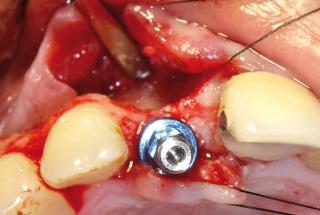

Clinical cases

MPI closely monitors clinical cases in the market to ensure their correct functioning and successful outcome.